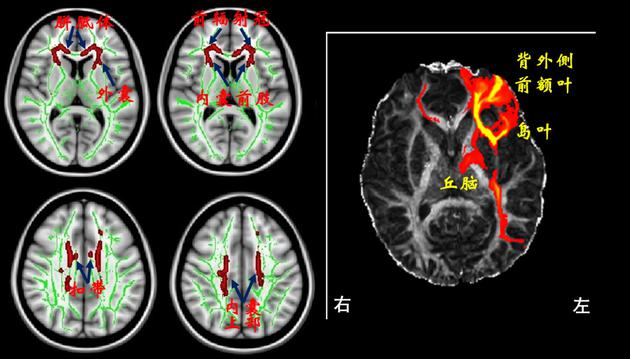

其实,我自己玩《王者荣耀》并不全是好奇或是觉得这游戏好玩,还有一个重要的原因就是“网络游戏成瘾”是我研究的一个课题。在2010年左右,我们团队与上海精神卫生中心、上海仁济医院合作研究发现:青少年网瘾患者伴随有大脑结构与功能的异常。研究选取了35名14~21岁的青少年作为被试,其中有17名青少年有网络(游戏)成瘾的问题。将这35名青少年脑部的磁共振图像进行对比发现:网瘾青少年大脑中一些白质纤维束,包括胼胝体膝部、外囊、内囊、辐射冠、扣带等存在微观结构上的异常。这种白质异常的模式与英国科学家在鸦片依赖患者中看到的结果类似,且左侧外囊异常程度与网瘾严重程度显著相关。相关研究还发现:网瘾青少年大脑前扣带回等脑区有明显的萎缩现象;一些大脑区域之间的功能连接也存在异常。这也就是说网络(游戏)成瘾不仅仅是不好的行为习惯或心理/精神层面的障碍,还伴随有大脑器质性的异常。

磁共振图像显示网瘾青少年大脑中的一些白质纤维束存在微结构异常(左图,箭头所指的红色区域)。其中,左侧外囊的异常部位是连接背外侧前额叶(DLPFC)、岛叶和丘脑这些脑区间信息交互的重要通道(右图)。网瘾越严重,此处的异常越显著

磁共振图像显示网瘾青少年大脑中的一些白质纤维束存在微结构异常(左图,箭头所指的红色区域)。其中,左侧外囊的异常部位是连接背外侧前额叶(DLPFC)、岛叶和丘脑这些脑区间信息交互的重要通道(右图)。网瘾越严重,此处的异常越显著2010年的时候还没有《王者荣耀》和《吃鸡》。人们玩的网络游戏主要是《魔兽争霸》,还有稍后一点的《英雄联盟》。这类游戏有个共同的专业名称叫做“多人线上竞技场游戏”,用英文字母缩写的话也叫MOBA游戏。这类游戏的特点就是多名玩家通过网络在线上临时组队,各自扮演不同的英雄角色,然后在一个虚拟的竞技场内按照游戏设定的规则捉对厮杀,直到分出胜负。《魔兽争霸》和《英雄联盟》这两个游戏都是美国出品,需要在台式电脑上玩,还要求电脑有比较高的配置和比较好的显卡。我没玩过、也不会玩这两个游戏。《王者荣耀》出来后,我像大多数玩家一样发现玩网络游戏原来不需要台式电脑、不需要好显卡、也不需要网线:只要有个手机或iPad,有4G网络,就可以随时随地玩,十分容易也十分方便。有一次看到儿子在玩,我突然脑洞大开,心想总不能整天说自己是研究网络游戏成瘾的,却什么游戏都不会玩吧?这岂不成了闭门造车、纸上谈兵。何不跟儿子一起玩玩看?一来支持一下国货,二来知道儿子到底在玩什么,三来也可以通过亲自体验加深对MOBA游戏的理解。一石三鸟,何乐而不为!于是,我也正式成为了“农药”的粉丝之一。